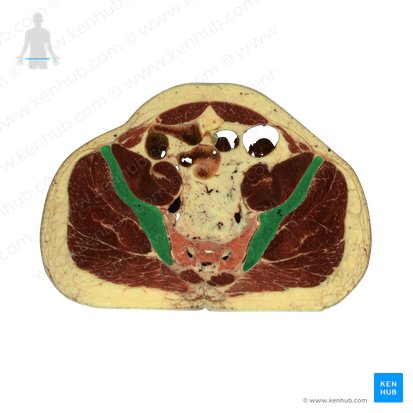

O ílio, também chamado de osso ilíaco, é o maior e mais superior dos três componentes da bacia.

Ele tem uma porção inferior menor, que contribui para a formação do acetábulo, e uma porção maior superior (ou asa) que se estende em forma de leque e fornece apoio ao abdome inferior (ou pelve falsa).

Os outros dois componentes da bacia são o ísquio, que forma sua porção posterior e inferior, e o púbis (ou osso púbico), que se localiza anteriormente. Os três componentes da bacia se unem no acetábulo.